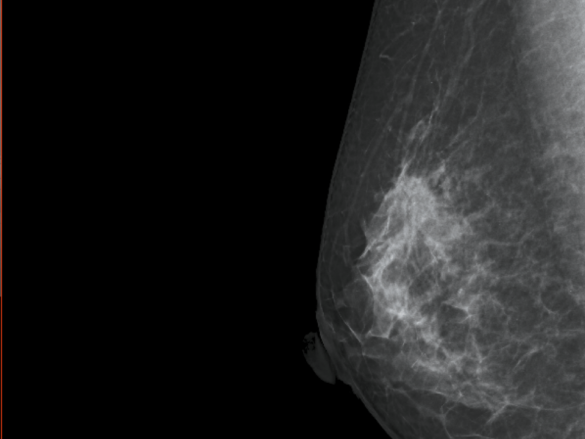

Imagem – Divulgação Fujifilm: exame de mamografia em 3D com tomossíntese apresentando massa hiperdensa durante rastreamento médico.

A tomossíntese oferece uma visão aprimorada da mama, permitindo que radiologistas identifiquem lesões mamárias de maneira mais acurada. “Esta abordagem tridimensional reduz a sobreposição de tecido mamário, tornando mais fácil a detecção de pequenos tumores e lesões suspeitas, muitas vezes imperceptíveis em mamografias tradicionais. Isso é muito relevante, considerando-se que o câncer de mama é o tipo que mais acomete mulheres em todo o mundo, incluindo o Brasil,” afirma Josemaria Pereira de Francesco, especialista de produtos Raio-X da Fujifilm.

O exame também demonstra uma significativa redução na taxa de falsos positivos em comparação com a mamografia convencional. Isso não apenas ajuda a evitar procedimentos invasivos desnecessários, mas também proporciona às pacientes uma maior tranquilidade durante o processo de triagem.